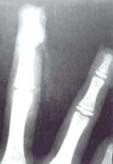

Confirmamos también que la articulación IFP depende casi exclusivamente de tres arterias: La arteria de la APTP, metafisiaria de F2 y la arteria dorsal de F2. La arteria de la APTP penetra en todos los casos a nivel de la polea C1, siendo esto un reparo anatómico importante en la clínica. La arteria metafisiaria de F2 en 31 de 32 casos, formo un arco anastomótico pequeño distal a la IFP, nutriendo la parte distal de esta articulación. —Arcada palmar mediana.

- Yousif NJ, Cunnagham W, Sanger JR Gingrass RP Matloub HS: The vascular supply to the proximal interphalangeal joint. J H, Surg, 1985; 10A; 852.